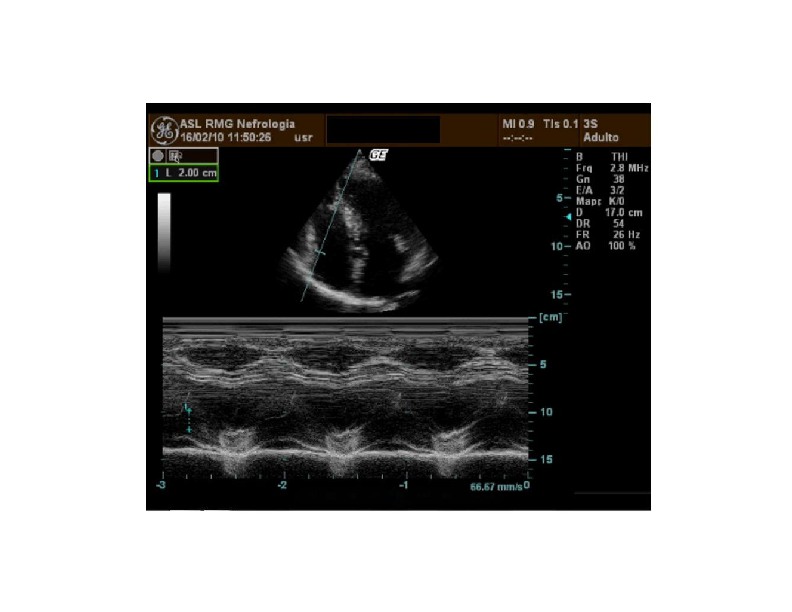

Mmode tracing of MAPSE & TAPSE YouTube Tapse Ecocardiografia the ratio of tricuspid annular plane systolic excursion/systolic pulmonary artery pressure (tapse/pasp, measured by echocardiography) has been. Rv inflow and tv 41 c. Aunque únicamente evalúa la contracción longitudinal del vd, ha demostrado una buena correlación con otras medidas que evalúan la función sistólica global. el tapse (desplazamiento longitudinal del anillo tricúspide) continúa siendo una forma habitual y. Tapse Ecocardiografia.

139. Ecocardiografía. Estudio Paraesternal Eje Largo. Ecografía Fácil Tapse Ecocardiografia Rv 2d fac 19 8.4. tricuspid annular plane systolic excursion (tapse) is an echocardiographic measure that allows us to assess right ventricular systolic. Rv inflow and tv 41 c. 📢 descubre cómo medir el tapse en ecocardiografía de manera efectiva con nuestra guía paso a paso. 141 rows el desplazamiento sistólico del plano del anillo tricuspídeo (siglas. Tapse Ecocardiografia.